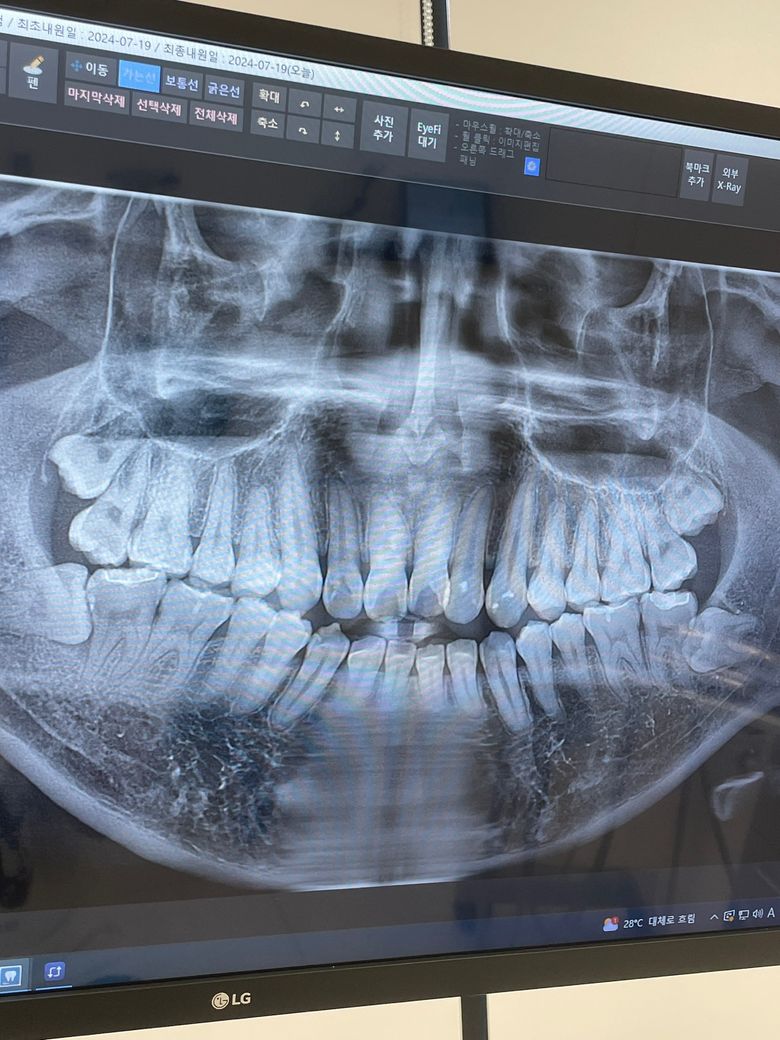

사랑니가 어금니를 녹여버리는 경우도 있나요..?

24년도 당시 엑스레이 입니다.

군 입대 전 치아의 머리가 나와있는 사랑니는 뽑았고 아직 사진상 오른쪽 사랑니는 뽑지 않았습니다. 가끔 욱신거리는 통증이 있긴 한데 일상생활에 지장도 없고 군대에 있는지라 발치가 어려운데 이제 전역을 앞두고 두달정도 휴가를 나가서 발치하려고 합니다. 휴가가 6월쯤 되는데 사진상으로 봤을때 어금니에 문제가 생겼을 가능성이 있을까요…? 양치는 꼼꼼히 하고 자기 전에는 무조건 했습니다. 식사 후에도 되도록이면 했구요…

현재 사진만으로는 정확히 알 수는 없습니다. 치아끼리 중첩되어 보여서 사랑니와 맨 뒤쪽 어금니가 중첩되는 부위의 평가가 어렵습니다. 이러한 경우에는 dental-ct까지 찍어보아야 합니다.

사랑니 역시 앞쪽 치아에 영향을 줄 수 있어 일부는 치아 뿌리를 녹일 수도 있고, 사랑니로 인하여 앞쪽에 음식물이 끼어 충치 등이 발생하는 경우도 많습니다.

매복 사랑니가 그 옆 어금니의 뿌리를 흡수시키는 건 충분히 있을 수 있는일입니다

사진상으로도 꽤 근거리에 두 치아가 겹쳐 있어서 영향을 줬을 가능성이 있습니다